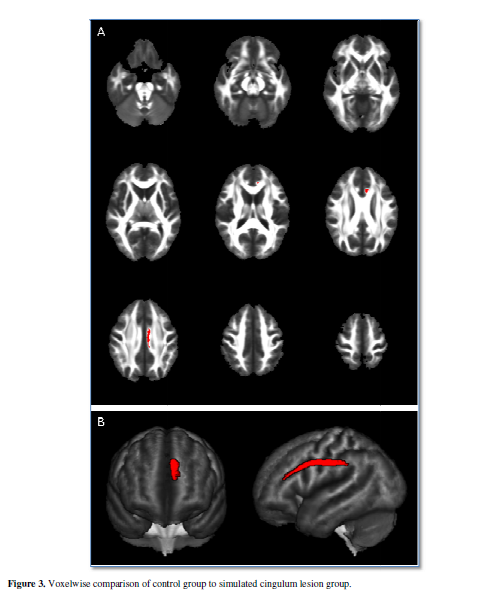

Voxelwise comparison of the

control group to the simulated corticospinal lesion group demonstrated

significantly decreased FAFI values in nearly every voxel of the main body of

the corticospinal tract (Figure 2).

Similarly, voxelwise comparison of the control group to the simulated cingulum

lesion group demonstrated significantly decreased FAFI values in nearly every

voxel of the main body of the cingulum (Figure

3). When voxels with abnormal FAFI values were rendered in three

dimensions, the affected tract was revealed in sufficient detail to identify it

based on its gross anatomy. There was no need for post-hoc tractography.

In both simulated lesion

groups, no voxels demonstrated increased FAFI values. Decreased FAFI values

were found exclusively in the left cerebral hemisphere (i.e. there were no

falsely discovered voxels in the right hemisphere).